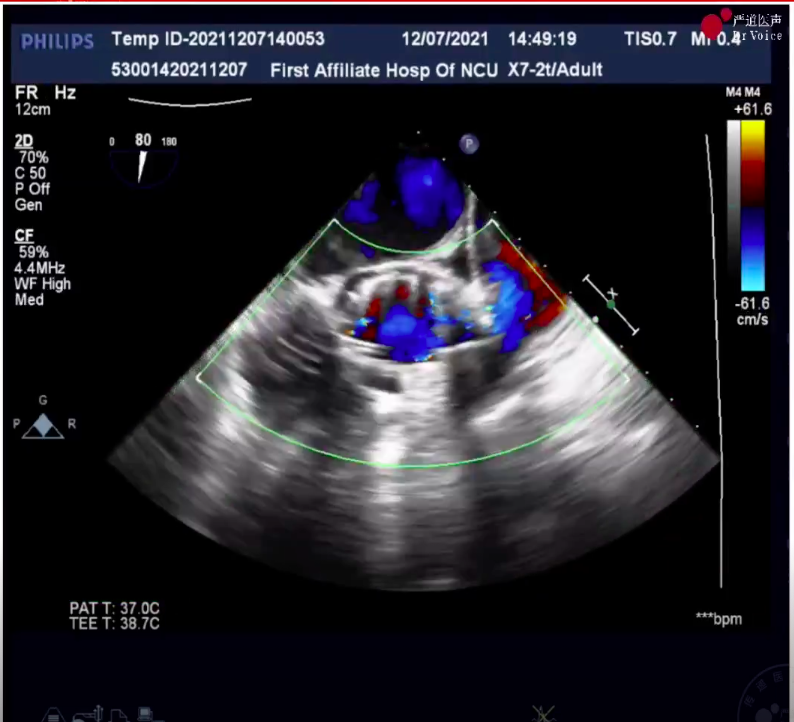

5、撤回输送系统,造影和食道超声显示基本无反流,患者术前舒张压47/48mmHg,术后显示68mmHg,无压力差,无瓣周漏,整台手术圆满完成。

术后造影及超声检查